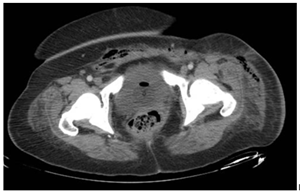

A 43-year-old female with morbid obesity (BMI 42), a history of type 2 diabetes diagnosed 12 years ago without treatment or follow-up, one cesarean section in 2011 and bilateral tubal occlusion in 2018. Who begins with sudden pain in the left inguinal region associated with swelling. She received analgesic treatment without improvement and decided to attend the hospital where is diagnosed with septic shock secondary to soft tissue infection. The results of the blood cytometry were leukocytes 21 000/mm, neutrophils 89%, lymphocytes 6%, hemoglobin 9 mg/dL, hematocrit 28%, and platelets 21 000/mm. Surgical drainage was done and a vulvar abscess was found, dissecting from the mount pubis to the ischiopubic fossa with necrotic tissue and fetid purulent material. During her postoperative period, she continued with purulent secretion outflow; a tomographic study showed the presence of fluid between the subcutaneous cell tissue and the muscular abdominal wall associated with subcutaneous emphysema (Figure 1 & 2). A reintervention was decided for surgical debridement and lavage, among the findings were: labile tissue with fetid necrotic edges, purulent secretion from the left genital area, inguinal region, abdominal subcutaneous cell tissue to the external oblique aponeurosis (Figure 3). In the postoperative period, multiple surgical lavages and debridements were carried out, followed by a VAC system. Nutritional parameters were below the acceptable level, parenteral nutrition was started and enteral nutrition with arginine boluses. A curve of nutritional parameters (albumin, prealbumin, ferritin and transferrin) was made prior to the establishment of the VAC system (Figure 4 & Table 1).

Figure 2 CT scan that reveals the extension through the abdominal wall.